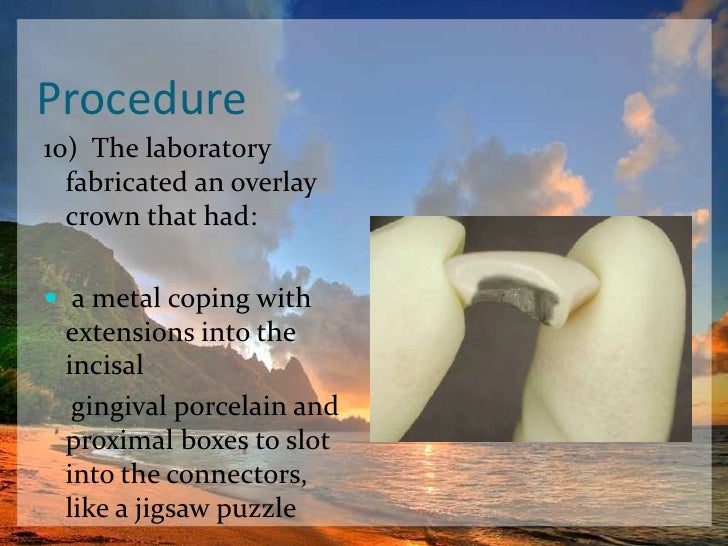

Repairing Fractured Pfm | PPT

Repairing Fractured Pfm

Repairing Fractured Pfm

Repairing Fractured Pfm

Repairing Fractured Pfm

Repairing Fractured Pfm